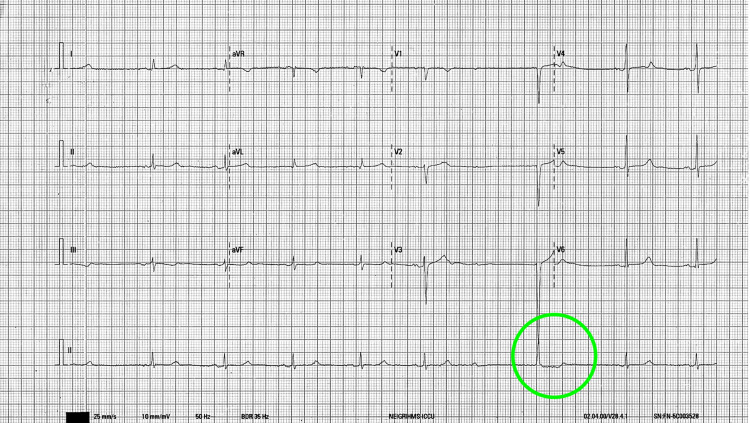

A 26-year-old otherwise healthy male presented to emergency with complaints of dizziness and recurrent syncope. At presentation, his pulse was 42/min, blood pressure: 100/70 mmHg, temperature: 98.1°F, and respiratory rate: 16/min. The rest of the physical examination was unremarkable. ECG on presentation showed a high-grade AV block along with sinus node dysfunction (Figures 1–2).

There was no improvement in the heart rate by repeated administration of atropine (total up to 3 mg). The patient admitted to using cannabis for the last four years, and in the preceding two years, he was smoking 5-8 joints (4-5 g) daily. Prior ECG was within normal limits; therefore, ruling out congenital heart block. There was no family history of any heart disease. The blood counts and metabolic panel were within the normal limit. Serological tests for syphilis, Lyme disease, hepatitis B, hepatitis C, and HIV were negative. Serial troponin-I reports did not show any elevation and the patient’s thyroid-stimulating hormone was normal. Urinary screen 11-Nor-9-carboxy THC was positive (28 ng/ml; cut-off limit: 15 ng/ml). The other biochemistry values are presented in Table 1.